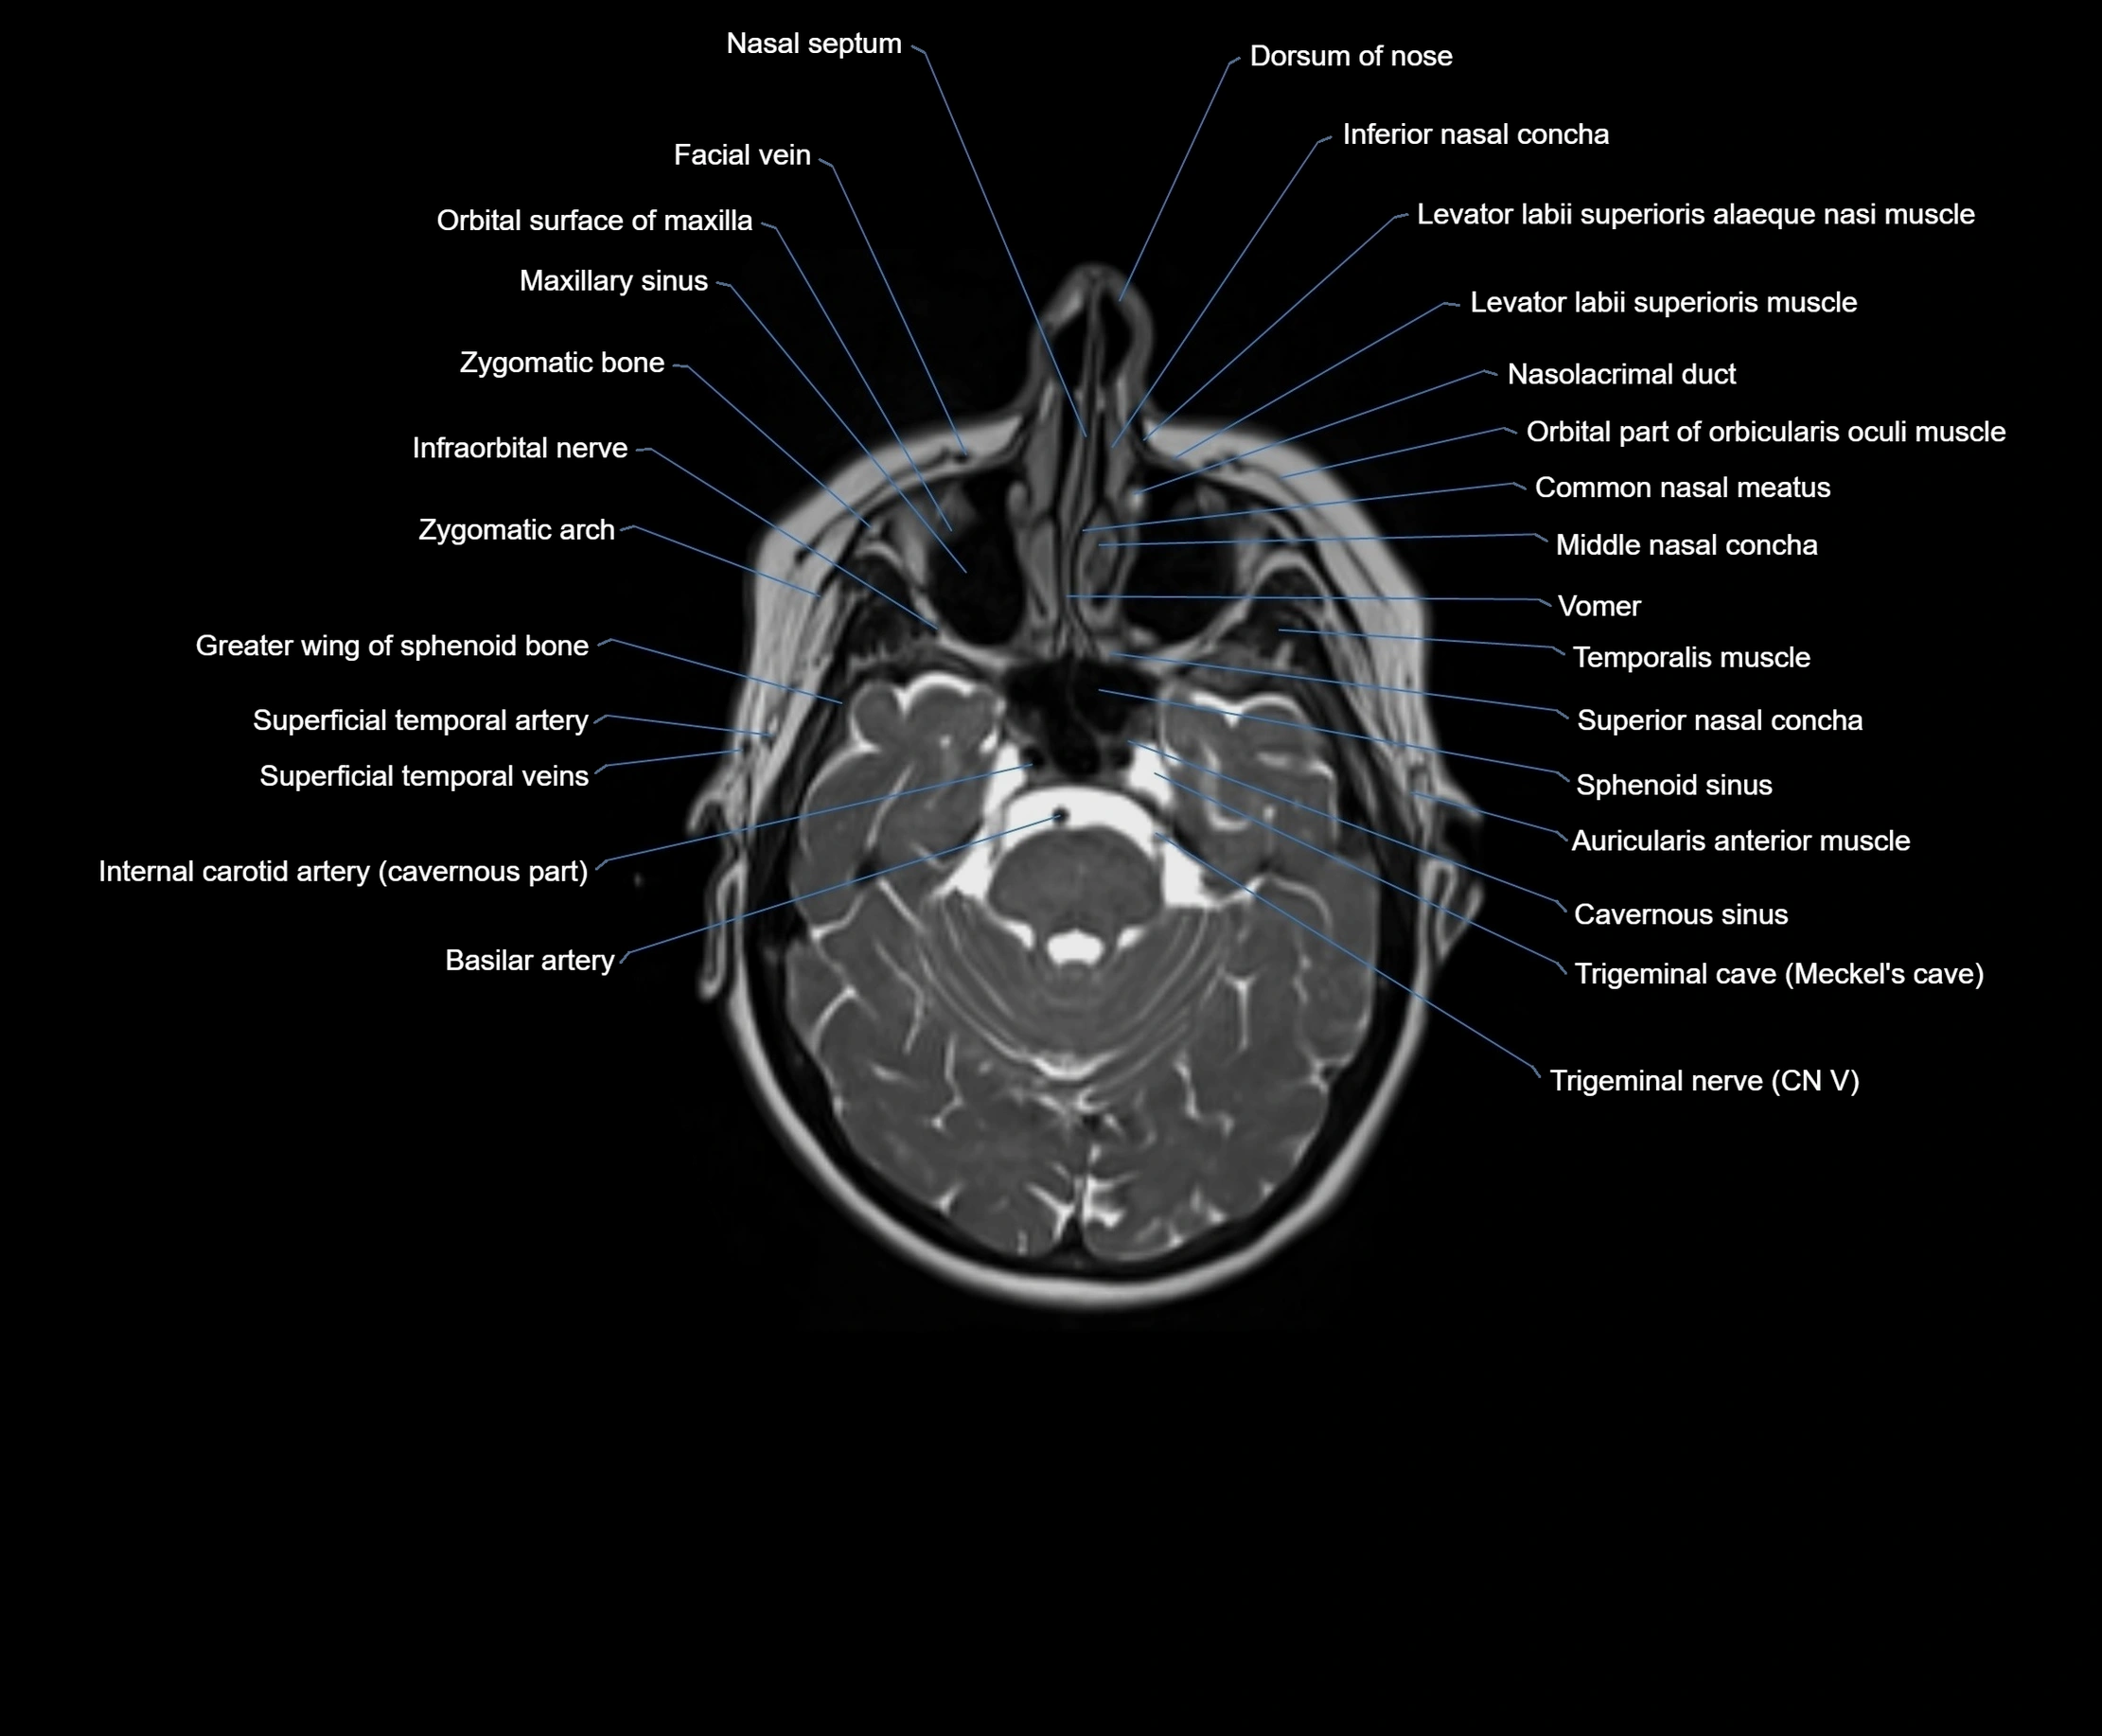

- Common nasal meatus

- Greater wing of sphenoid bone

- Inferior nasal concha

- Internal carotid artery (cavernous part)

- Internal carotid artery (petrous part)

- Middle nasal concha

- Motor nucleus of facial nerve

- Sphenoid sinus

- Superior nasal concha

- Trigeminal nerve (Cranial nerve V)